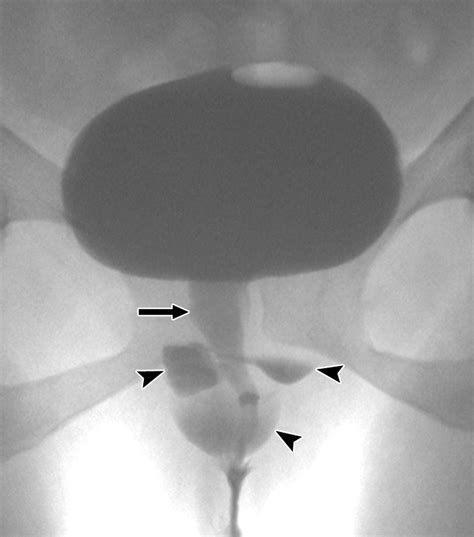

MRI (Magnetic Resonance Imaging) The gold standard for visualizing the size and location of the diverticulum.

Voiding Cystourethrogram (VCUG) Uses contrast dye to see if the pouch fills during urination.

Urethroscopy Direct visualization of the urethra using a thin camera to locate the diverticular opening.